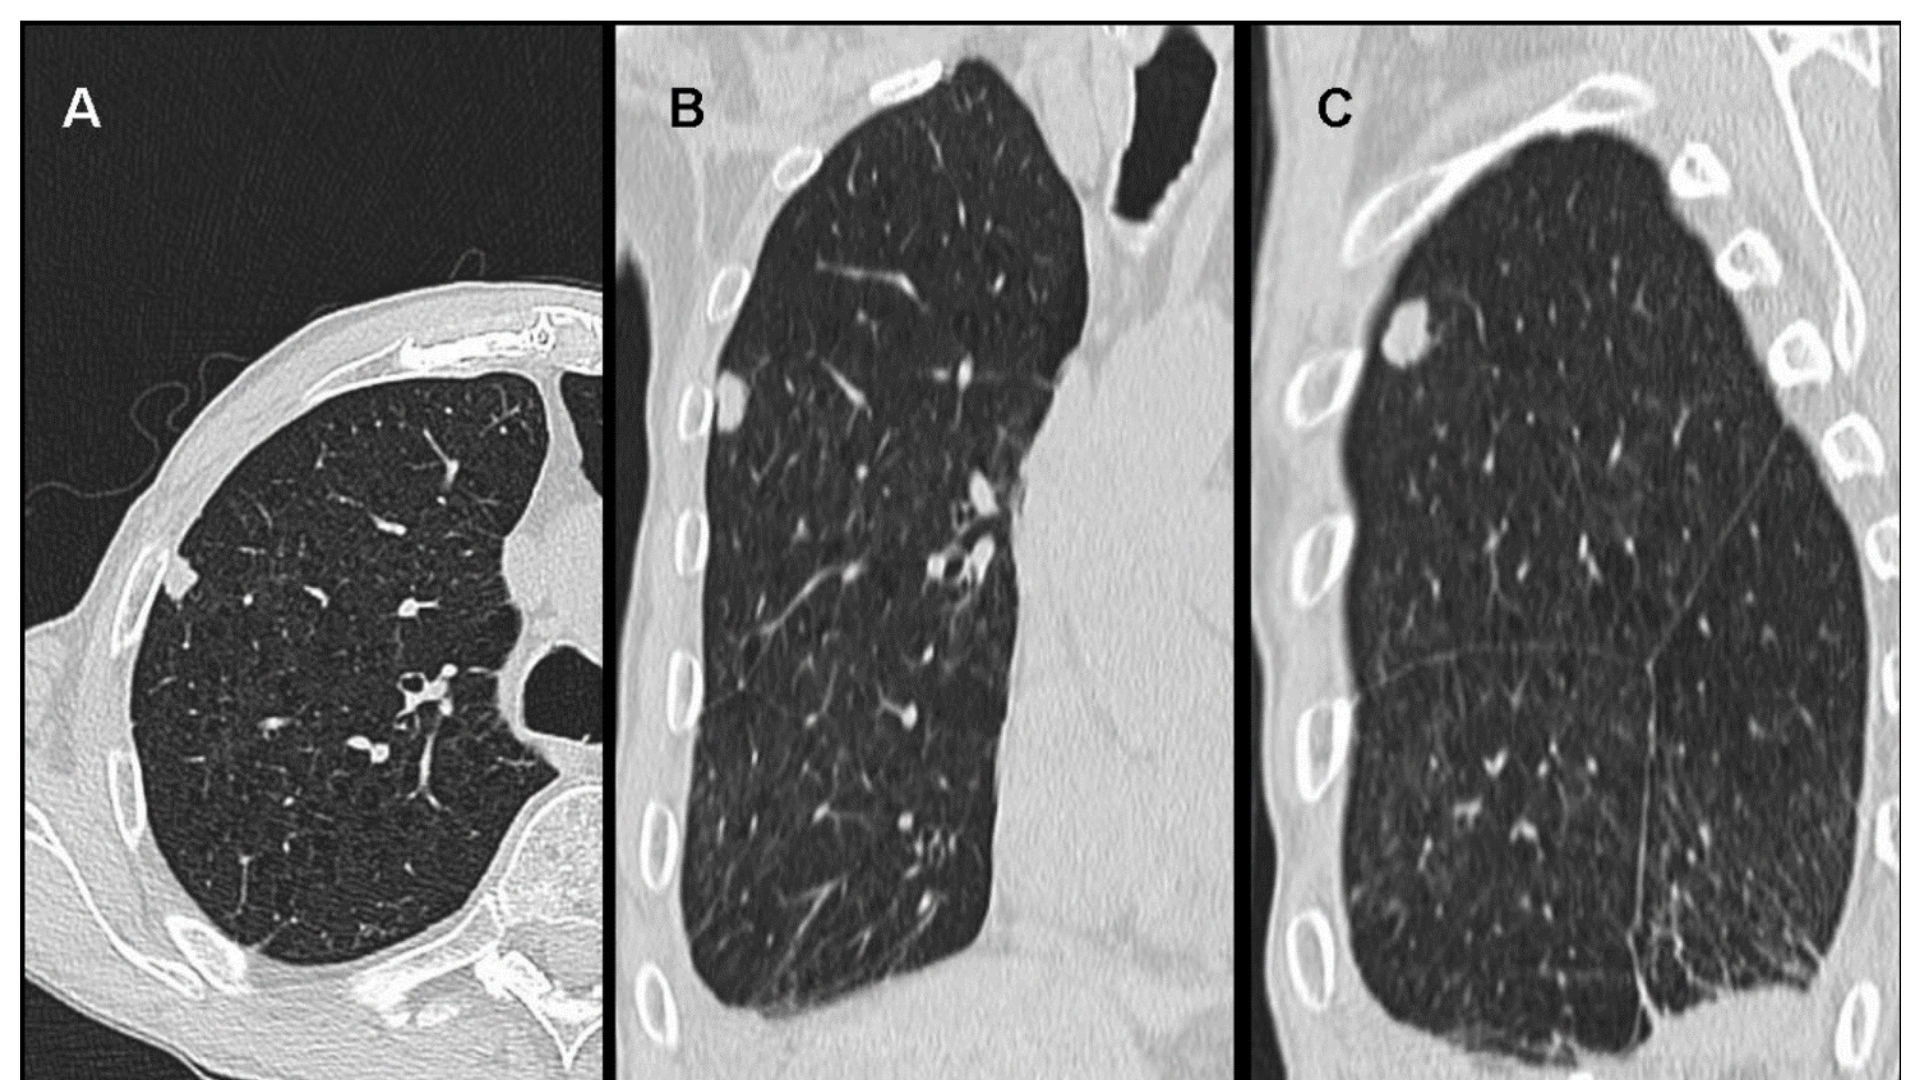

• 進階診斷:最先進的影像(例如 PET-CT、Siemens MRI)和分子剖析,以找出腫瘤的代謝漏洞。

• 醫療記錄:最近的診斷報告、影像掃描(如 CT、MRI、PET-CT)、病理結果和治療史。接受數位或實體複本。